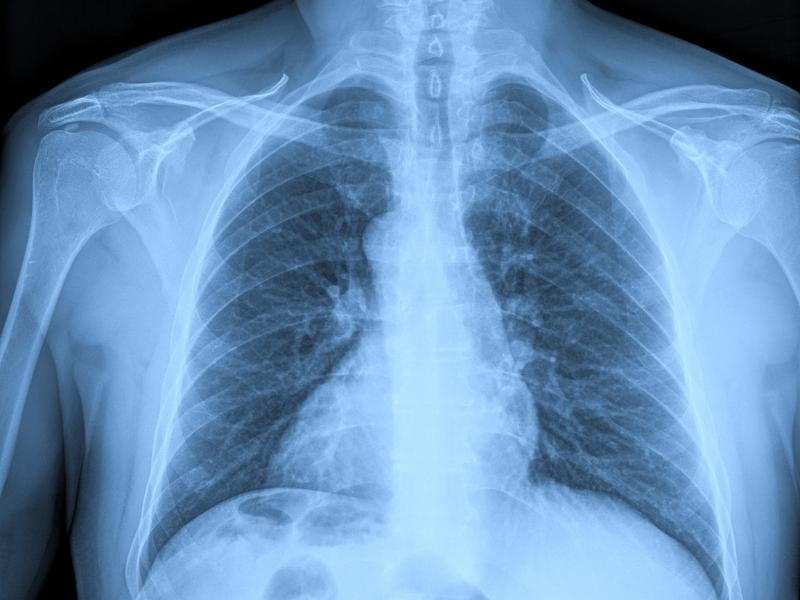

O Laudo OIT é um exame essencial para avaliar possíveis alterações pulmonares relacionadas à exposição ocupacional a poeiras, gases e outras substâncias nocivas. Baseado nos padrões da Organização Internacional do Trabalho (OIT), esse exame é indicado para trabalhadores de áreas industriais, mineração, construção civil e outras atividades de risco. Em Porto Alegre, a Instamed oferece Laudo OIT com tecnologia avançada e profissionais altamente qualificados.

O Laudo OIT é um exame radiológico específico que segue a classificação padronizada da Organização Internacional do Trabalho para avaliação de pneumoconioses e outras doenças pulmonares ocupacionais. Esse exame é fundamental para detectar precocemente alterações pulmonares causadas por exposição prolongada a substâncias inalatórias nocivas. Na Instamed, garantimos um exame seguro e preciso para um diagnóstico confiável.

O exame de Laudo OIT é realizado por meio de uma radiografia torácica padronizada, seguindo critérios rigorosos estabelecidos pela Organização Internacional do Trabalho. A interpretação das imagens é feita por médicos especializados em radiologia ocupacional, garantindo um diagnóstico preciso. Na Instamed, utilizamos equipamentos modernos para assegurar a qualidade das imagens e um laudo confiável.